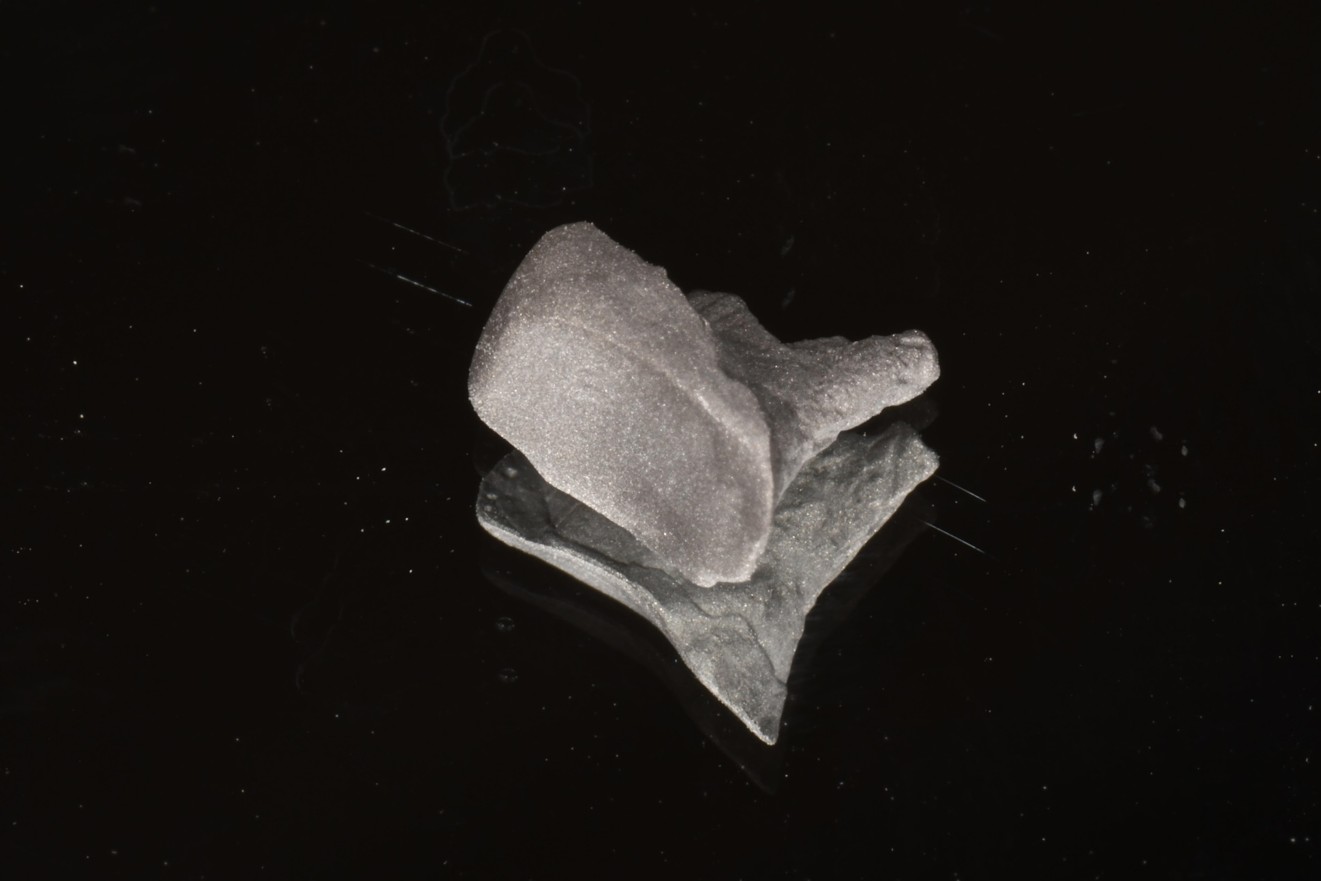

鑄造金屬釘柱